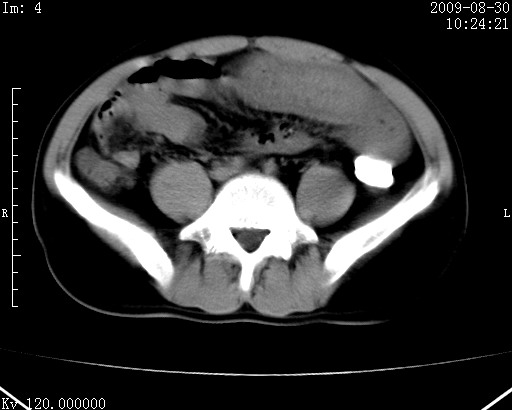

患者唐某,男31岁,已婚,本地务农。

自述入院前两天一次进食较多冷饮之后,出现阵发性上腹部疼痛,次日加剧伴恶心、呕吐,呕吐后症状稍减轻。食欲差。大便每天1-2次,量少,暗红色水样。小便赤。无畏寒、发热、咳嗽等呼吸道症状。无高血压及胃病史。

检查:体温、血压及脉搏正常.皮肤无黄染,浅表无淋巴结肿大。左腹肌紧张,左上腹有压痛,无反跳痛,可触及包块。

生化:钾、钠、氯、钙、ph正常,总胆红素和直接胆红素稍高,空腹血糖稍高。

尿淀粉酶:1256 u/l(正常60-401)。

血常规:wbc 22.4x109/l gr88% ly9.6%其余基本正常。

胃镜:急性胃炎。立位腹平片:未见异常。

下面是ct平扫,降结肠内是对比剂。

术前影像诊断:上段空肠急性缺血性坏死并腹水。建议手术治疗。

术中见上段空肠约70cm长范围坏死,从屈氏韧带远端约10cm处开始。坏死肠管肿胀变形变色,管壁明显环形增厚,部分聚成大肿块,无扭转和套叠。肠系膜上动脉分支内广泛泥沙状血栓。肠切除。

临床诊断:肠系膜上动脉梗塞并急性肠坏死。

开始时我们科也有人认为是套叠,最后统一意见,不考虑肠套。我们看到的“靶征”,“晕圈征”,“双圈征”实际上只是单根肠管的横断面。坏死肿胀后肠壁各层的密度不一样。

左侧腹小肠腔管壁明显增厚,部分内示靶征,走行异常,部分肠系膜绳样改变,肝包膜下及肠间较多液体密度,然梗阻近端肠腔积气不明显。

考虑;肠扭曲伴肠坏死。

有结果了,回顾分析,套叠只会在局部出现同心圆征,不会很长一段肠管都有,还是水肿坏死。